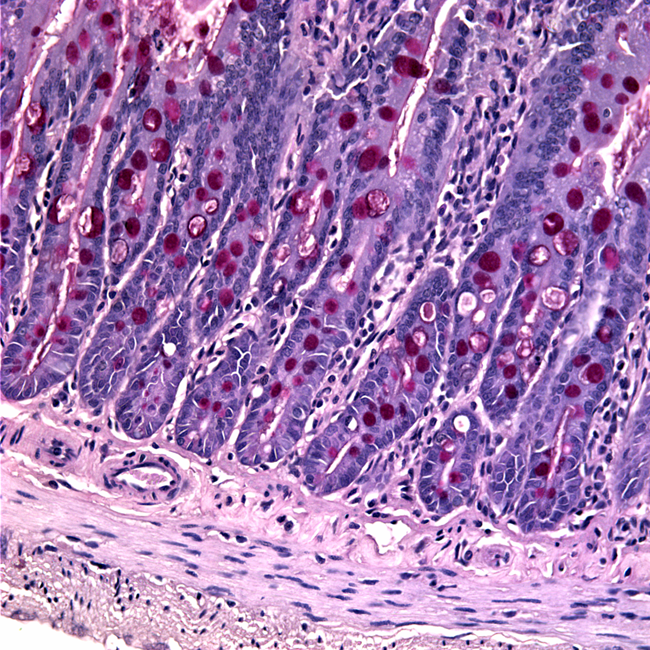

Have a look at some image samples our faculty has captured using the scanning electron microscopes (SEM), transmission electron microscopes (TEM), and light microscopes (LM) in the Advance Microscopy Facility (AMF).